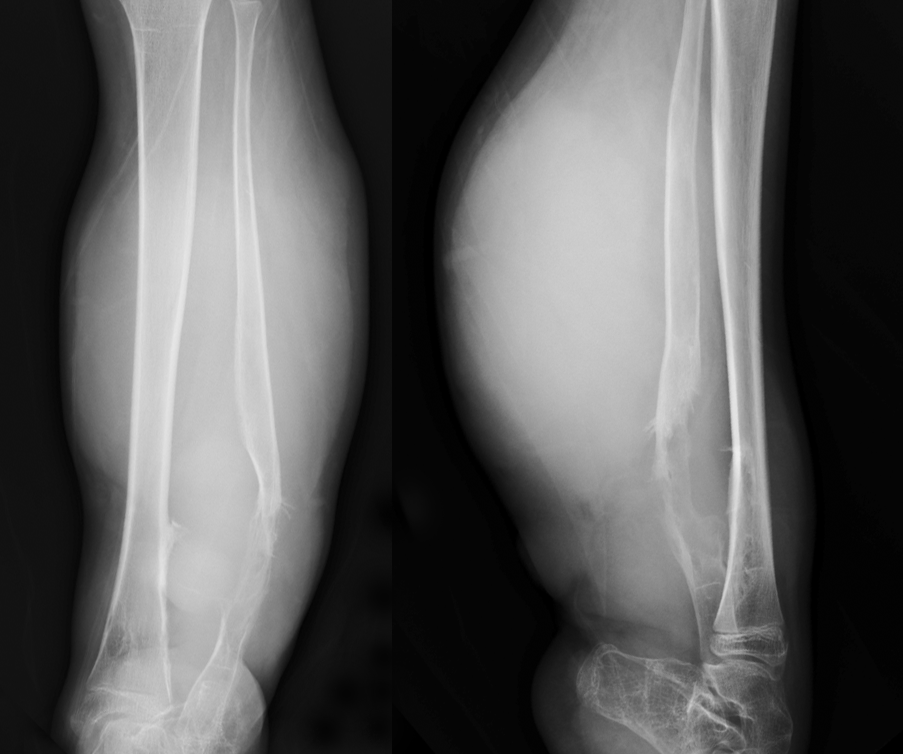

No.8

软组织肿块

软组织肿块是诊断恶性骨肿瘤重要依据。X 线平片、CT 及 MRI 均可用于软组织肿块的评估,X 线平片显示软组织肿块作用有限,表现为局部软组织密度增高影,边缘隐约可见(图 55),CT 和 MRI 显示软组织肿块明显优于 X 线平片(图 56、图 57),可清楚显示软组织肿块的大小、边缘轮廓外,还可清晰显示软组织肿块内部病理变化,对肿瘤定性诊断有帮助作用。对于软组织肿块影像学需重点观察其边缘、密度/信号均匀性,是否伴有钙化或骨化,增强扫描后强化特点以及瘤周是否伴发水肿等表现。

图片

图 55.软组织肿块:恶性骨巨细胞瘤

图 56.软组织肿块:骨软骨瘤恶变

图 57.软组织肿块:骨淋巴瘤